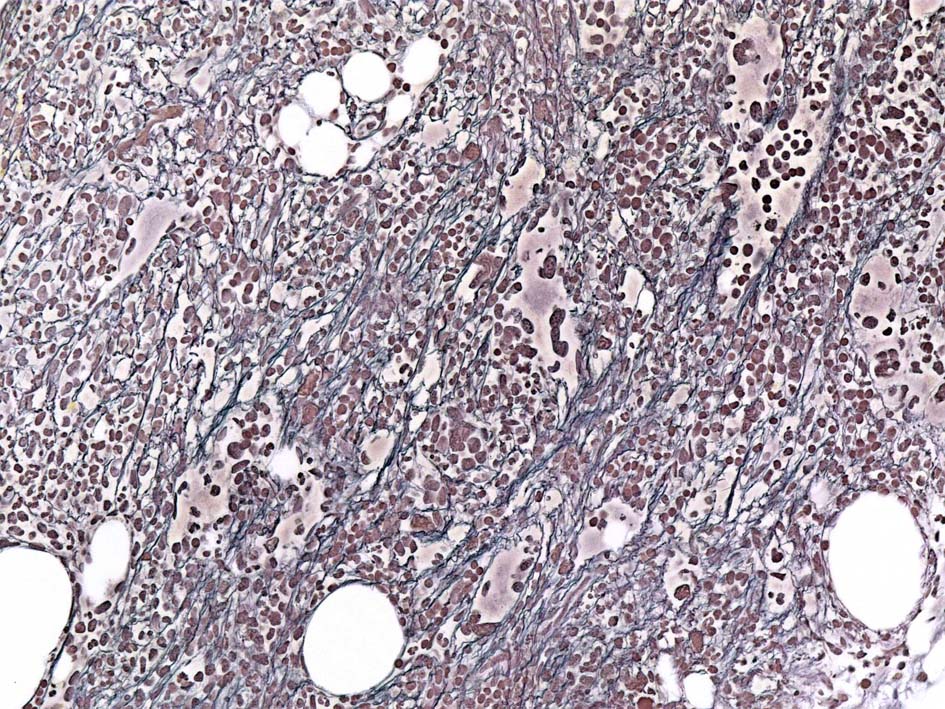

骨髄組織所見 bone marrow biopsy total 6mm in length

CD42b染色